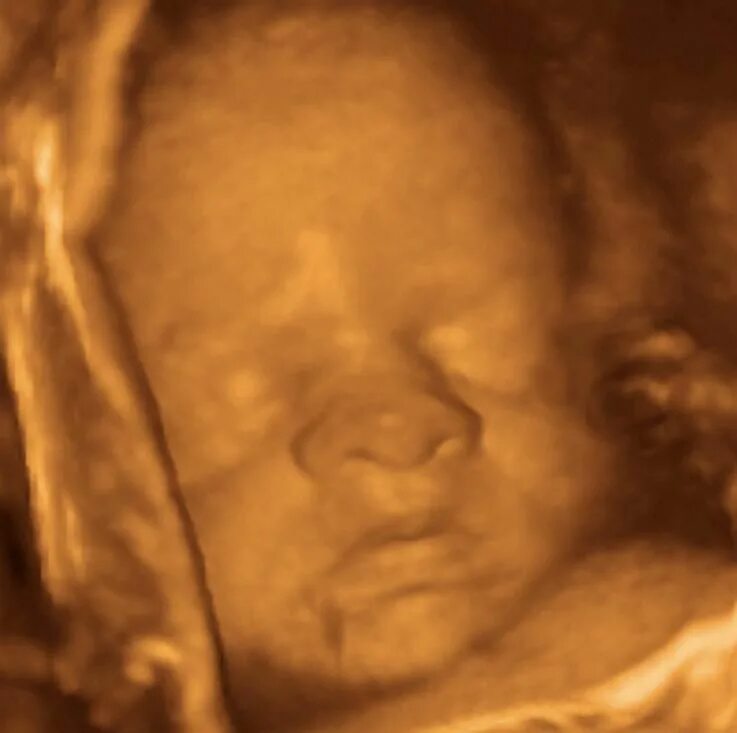

Девочка 30 недель